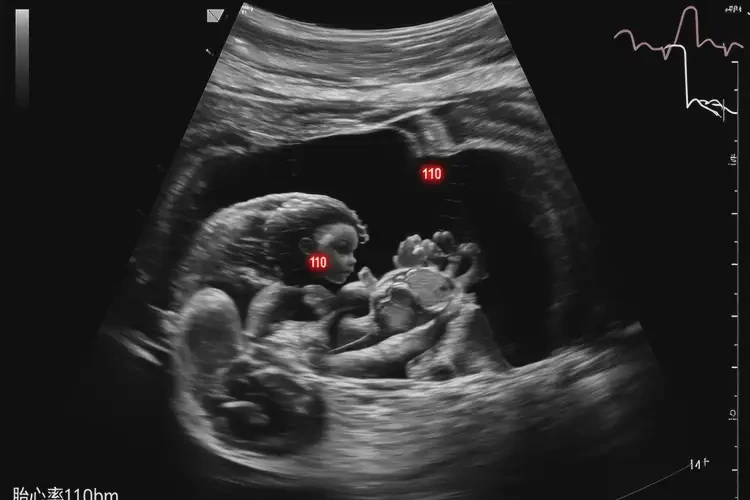

孕33周2天胎心110左右正常嗎

胎心率在110次/分鐘左右對(duì)于孕33周2天的胎兒來(lái)說(shuō)偏低。

正常情況下,孕33周的胎兒胎心率應(yīng)在120-160次/分鐘之間。胎心率低于120次/分鐘可能提示胎兒存在某些問(wèn)題,如胎兒窘迫或缺氧。胎心率的測(cè)量可能會(huì)受到多種因素的影響,包括胎兒的睡眠周期、孕婦的體位和情緒等。如果發(fā)現(xiàn)胎心率偏低,建議及時(shí)咨詢醫(yī)生進(jìn)行進(jìn)一步評(píng)估。

孕33周2天胎心110左右正常嗎(圖1)